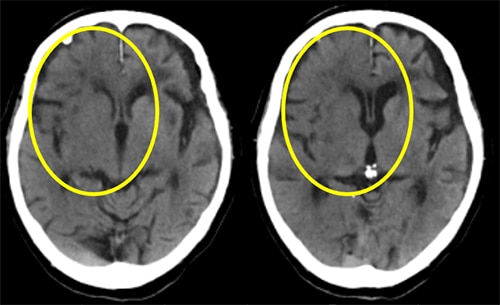

被ばく線量をDLPで比較した結果をFig.7,8に示します。

Revolution Ascend の導入後、頭部、胸部ともに平均DLPは明らかに低下し、頭部で約20%、胸部で約25%の被ばく低減が確認できました。前述の通り、線量低減させても画質は維持できており、これはTFI使用によるものと考えます。

Fig.7 各期間における被ばく線量の推移

Fig.8 各期間におけるDLP[mGy・cm]の平均値

また、3D DLカメラによる自動ポジショニングの導入後にはさらに被ばくを低減することができました。特に体幹部では平均DLPがさらに5%低下しており、これは自動ポジショニングによって技師の技量に依存せず、正確に患者の体厚中心にポジショニングできたことによるものと考えます。

現在の頭部の平均DLPは約1000、胸部の平均DLPは約320となっています。